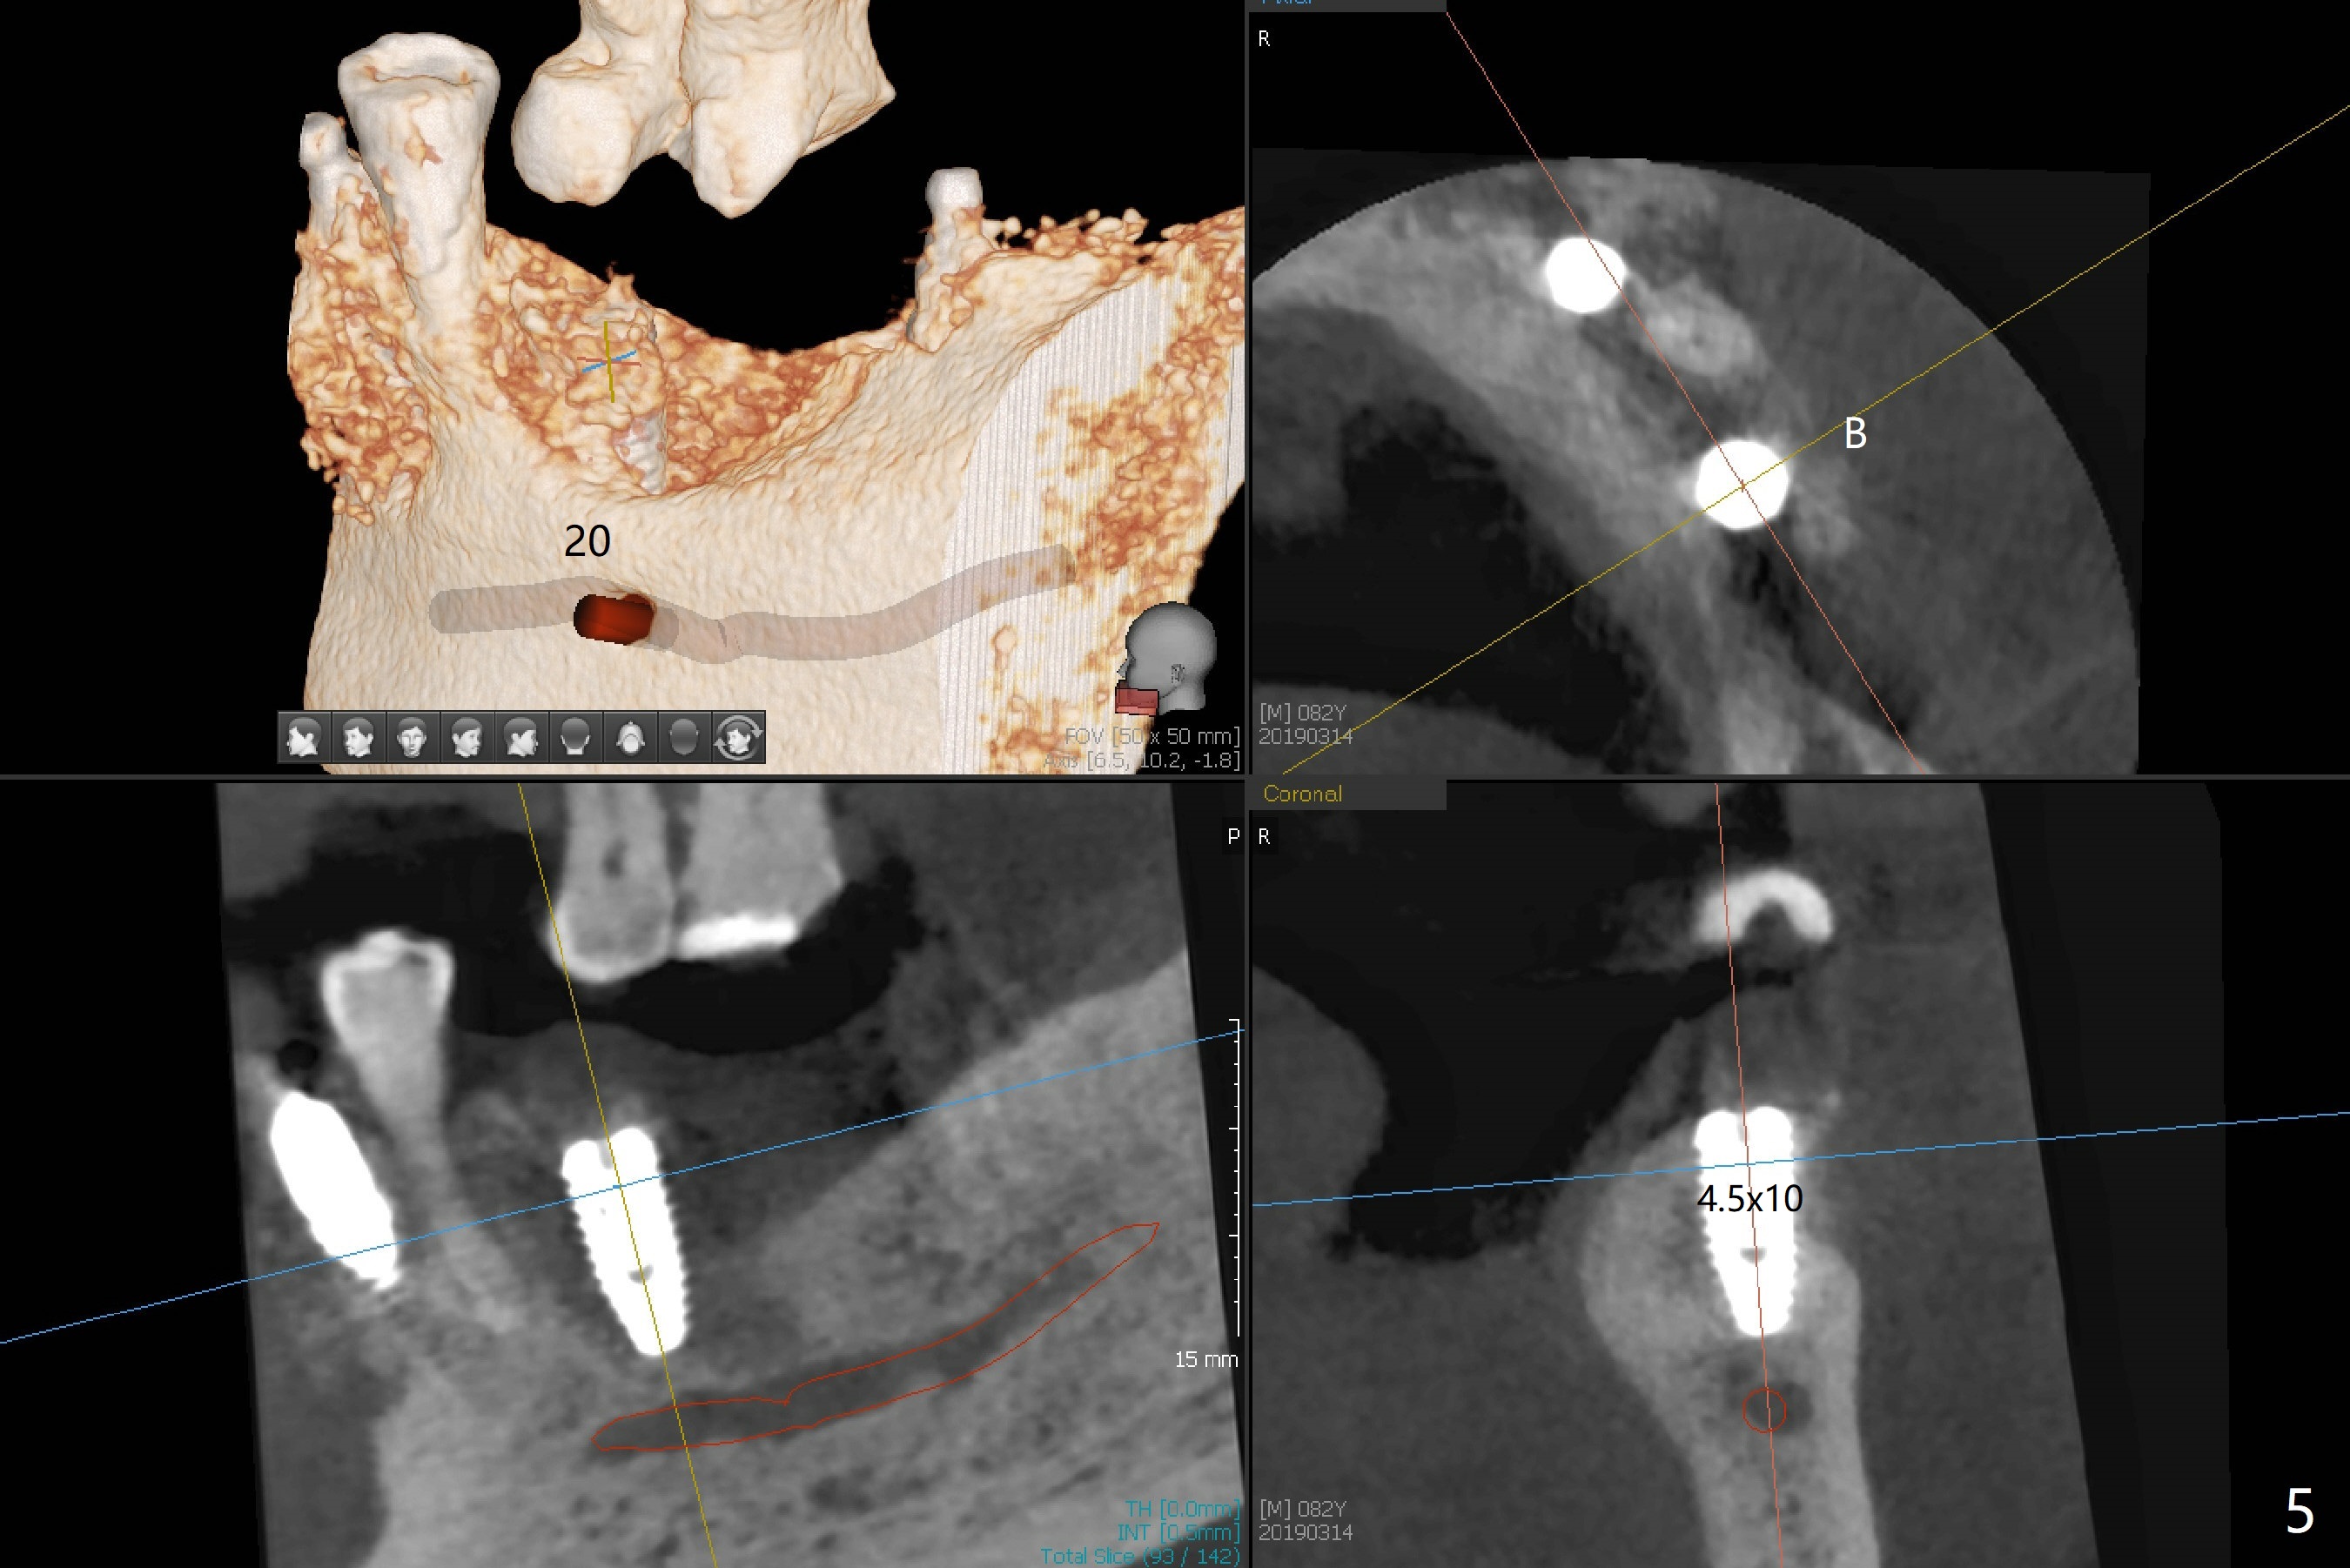

Three months post socket preservation (with buccal plate loss previously), a 3.5x11.5 mm implant is placed at #27 subcrestal (Fig.1). When implants are placed at #22 and 20 (Fig.2,4), threads are exposed buccal (B). Mixture of autogenous bone and allograft is placed to cover the exposed threads (Fig.3,5) following deep placement at #20. For safety, the implant at #20 is buried. Pain control at #18 is poor when initial osteotomy is being established (Fig.6 *), as related to severe infection. Repeated block anesthesia allows to finish implant placement with primary stability; a 3.5x2 mm ball abutment is placed (Fig.7). With placement of 2 other ball abutments at #27 and 22 (Fig.3), the lower existing RPD is converted to a removable provisional (Fig.8). With addition of acrylic, the socket of #20 is covered (Fig.9). There is no apparent bone #20 distal 3 months postop (Fig.10,11 <). Re-graft is needed? The implant at #21 appears immediately subgingival 5 months postop (Fig.12 *). The distobuccal threads are exposed (Fig.13). After decortication, allograft is placed, followed by 6-month membrane. In fact, a shorter and smaller implant should be placed instead. The patient has to wear the RPD for mastication. It would be more painful without it. Later the tissue surface of the RPD is trimmed.